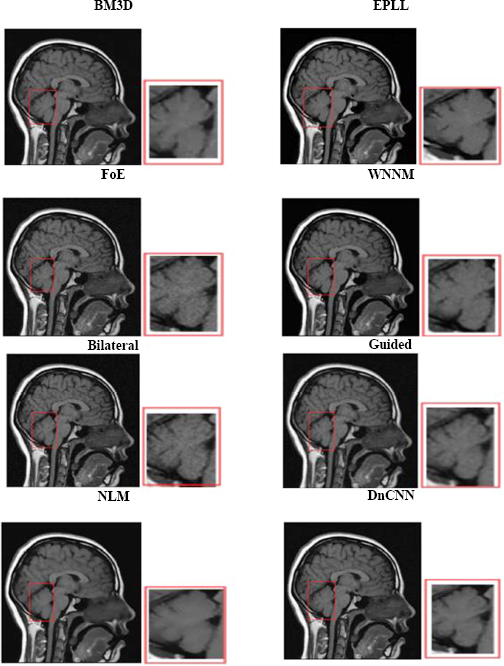

4.2. Visual Analysis

Visual analysis of the usual MRI and HRCT images is used to examine the qualitative performance of each denoising algorithm. Special attention was paid to anatomically relevant sites, such as fine pulmonary textures in HRCT and gray-white matter boundaries in T1-weighted brain MRI.

The visual quality of the denoised images was determined on cropped and zoomed regions of interest (ROIs). The capability of the algorithms to minimize noise while preserving the most essential features, such as tumor borders, ventricular boundaries, or alveolar boundaries, was tested. Such an analysis is crucial, especially in medical imaging, where even slight degradation or excessive smoothing may obscure diagnostic clues. Perceived quality and artifact suppression are illuminated by visual comparisons, and quantitative measurements are corroborated.